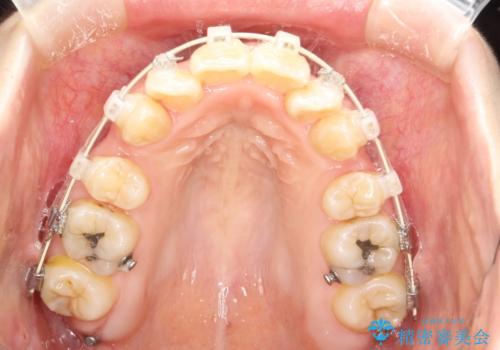

重度のガタガタ ワイヤーによる抜歯矯正

上下の歯に重度のガタガタがあり、前歯が下の歯と咬んでいない状態でした。

審美装置を用いた、抜歯矯正を行うこととしました。

抜歯したスペースを使うことで、ガタガタと出っ歯を改善することができました。